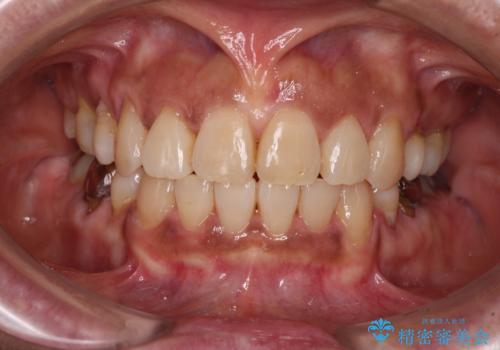

- 上下前歯のデコボコを気にして来院された患者様です。

歯列としては、ワイヤー装置でもインビザラインでも、どちらでも対応可能でしたが、処置されている歯が多く、ワイヤー装置を装着するためには処置歯のやり直しが必要な状態でした。

インビザラインでもアタッチメントを装着できないという同様のデメリットがありますが、比較的矯正治療を行いやすい歯列であったので、インビザラインによる矯正治療を行うこととしました。

術中や仕上がりに特に大きなトラブルはなく、スムーズに治療を終えることができました。